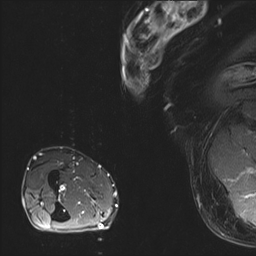

To evaluate model interpretability via DS and DSc\mathrm{DS}_{c}roman_DS start_POSTSUBSCRIPT italic_c end_POSTSUBSCRIPT, we apply both MoRF and LeRF occlusion strategies. In the MoRF strategy, we iteratively apply a Gaussian blur to the image regions deemed most salient by the interpretability method, progressively attenuating their visual information. Conversely, the LeRF strategy blurs the least salient regions first. An illustration of the MoRF process is shown in Figure 5. This figure presents a step-by-step example to clarify the procedure: starting with the original saliency map, we progressively blur the top 10% of pixels deemed most important by the model. This deletion continues in increments, such that by the 80% step, the majority of less relevant pixels are blurred, ultimately reaching 100% occlusion of the image. By measuring the change in the model’s prediction probability as each block of pixels is blurred, we compute DS and DSc\mathrm{DS}_{c}roman_DS start_POSTSUBSCRIPT italic_c end_POSTSUBSCRIPT as the area between the model’s output curves under the MoRF and LeRF interventions.

Refer to caption

(a) Original Image

(b) Interpretation

(c) 10% Blur

(d) 80% Blur

Figure 5: Progressive blurring of the image based on MoRF strategy.